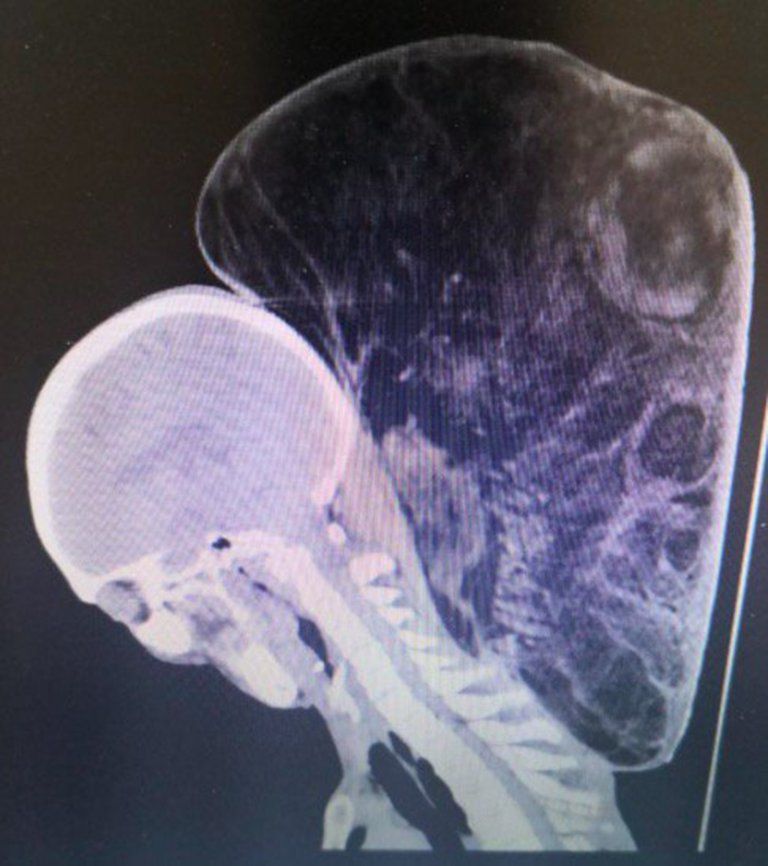

gif_animation これ、人間の写真らしい・・・。中国にて、17歳の頃から47年間、首に出来た腫瘍が成長し続け、15kgもの重さに達してしまった64歳男性の姿。家が貧しかったため治療を行う事が出来なかったが、最近お金が貯まったため、手術に踏み切ったよう。